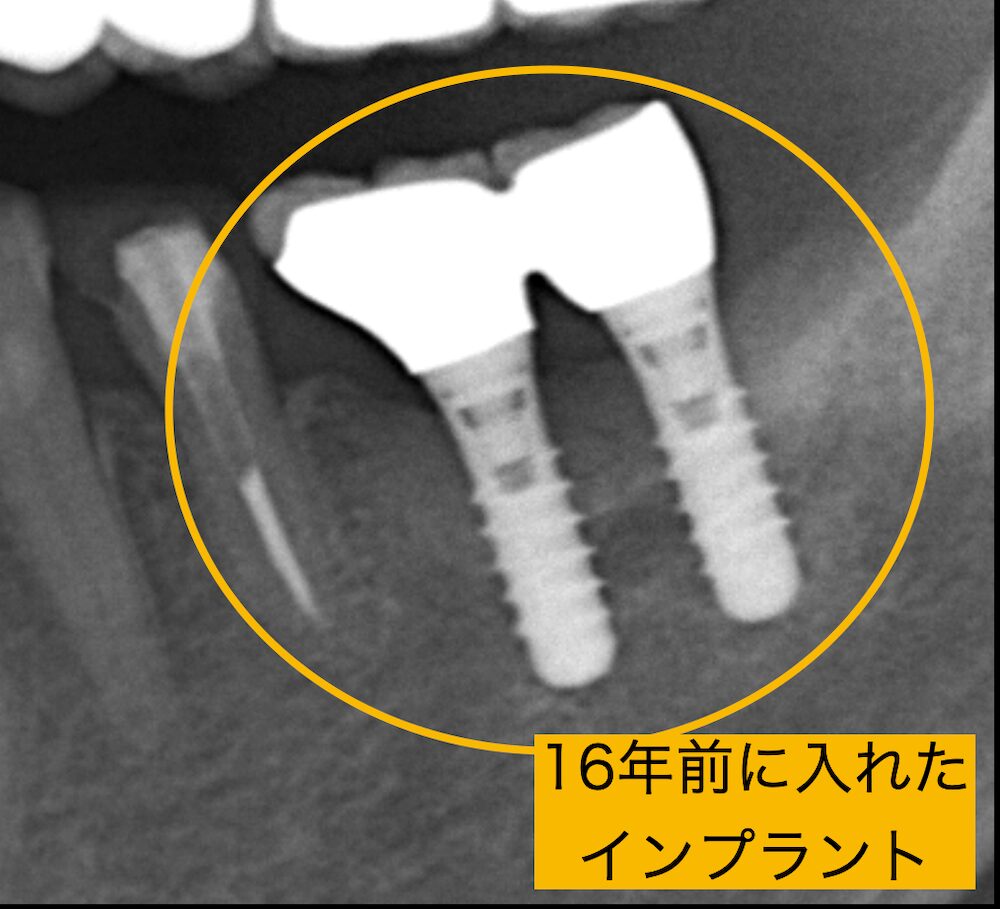

実際の症例

この患者様は16年前にインプラントを埋入されました。半年に一回のメインテナンスをしっかりと受けられ、日頃の歯ブラシも頑張っておられます。インプラントは16年間全く問題なく、周りの骨も16年ものあいだ、何一つ変わっておりません。この方はこれからもメインテンスに通われているかぎり毎日、惜しくご飯を食べていると思われます。

治療が終了したからといって、「もう歯医者に行かなくてもいい」というわけではありません。

その良い状態を長く維持するためには、定期的に通院する習慣が大切です。